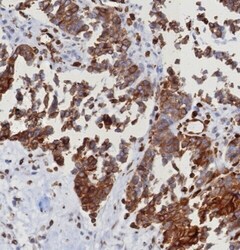

- Submitted by

- Invitrogen Antibodies (provider)

- Main image

- Experimental details

- Formalin-fixed, paraffin-embedded human spleen stained with STING1 Recombinant Rabbit Monoclonal Antibody (STING1/8187R). HIER: Tris/EDTA, pH9.0, 45 min. 2 °: HRP-polymer, 30 min. DAB, 5 min.